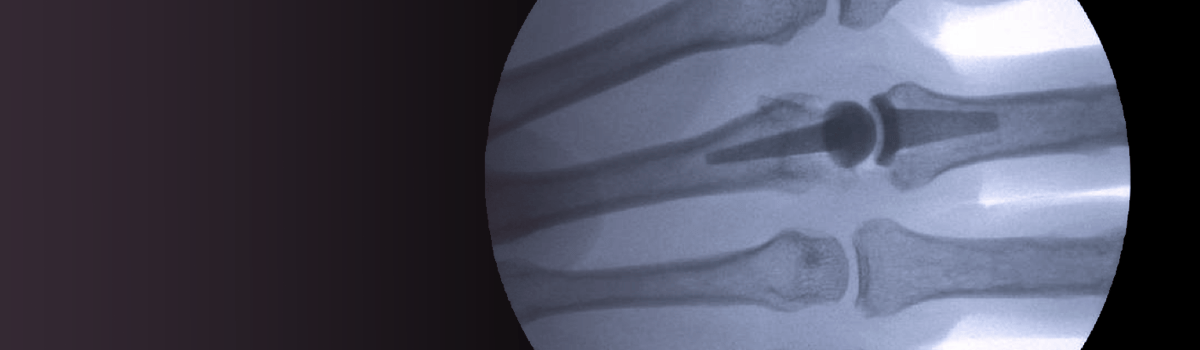

We are experts at treating arthritis throughout the upper extremity, whether from trauma, wear-and-tear, or inflammatory disease. We specialize in:

Joint replacement or fusion for finger joint arthritis